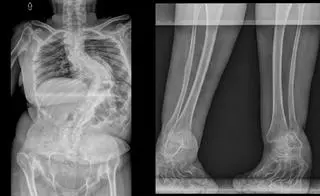

Paulina Zaborowska urodziła się z bardzo rzadką wadą genetyczną - dysplazją diastroficzną, która została u niej zdiagnozowana dopiero, gdy była nastolatką. Na tę samą chorobę cierpi jej starsza siostra, która także długo musiała czekać na diagnozę.

Jej choroba to jedna z najcięższych i najtrudniejszych do leczenia odmian karłowatości. Objawia się m.in. niskim wzrostem, skróceniem kończyn, nieprawidłowym ukształtowaniem stóp i dłoni, poważnymi deformacjami stawów oraz ich przedwczesnymi zwyrodnieniami. Z wiekiem deformacje stawów nasilają się i prowadzą do pogłębiającej się skoliozy kręgosłupa.

- To oznacza poważne problemy z poruszaniem się i stale nasilający się ból - mówi pani Paulina.

- Obecnie kondycja moich stawów odpowiada osobie w bardzo podeszłym wieku. Mam stawy, jak ktoś kto ma około 90 lat - przyznaje.

- Wcześniej udawało mi się jeszcze poruszać samodzielnie, teraz mogę chodzić tylko o kulach. Z uwagi na pogłębiającą się skoliozę, istnieje też ryzyko, że w przyszłości będę musiała jeździć na wózku inwalidzkim - mówi pani Paulina. I dodaje: - Jeśli okazałoby się, że operacja nie dojdzie do skutku, takie ryzyko rośnie.